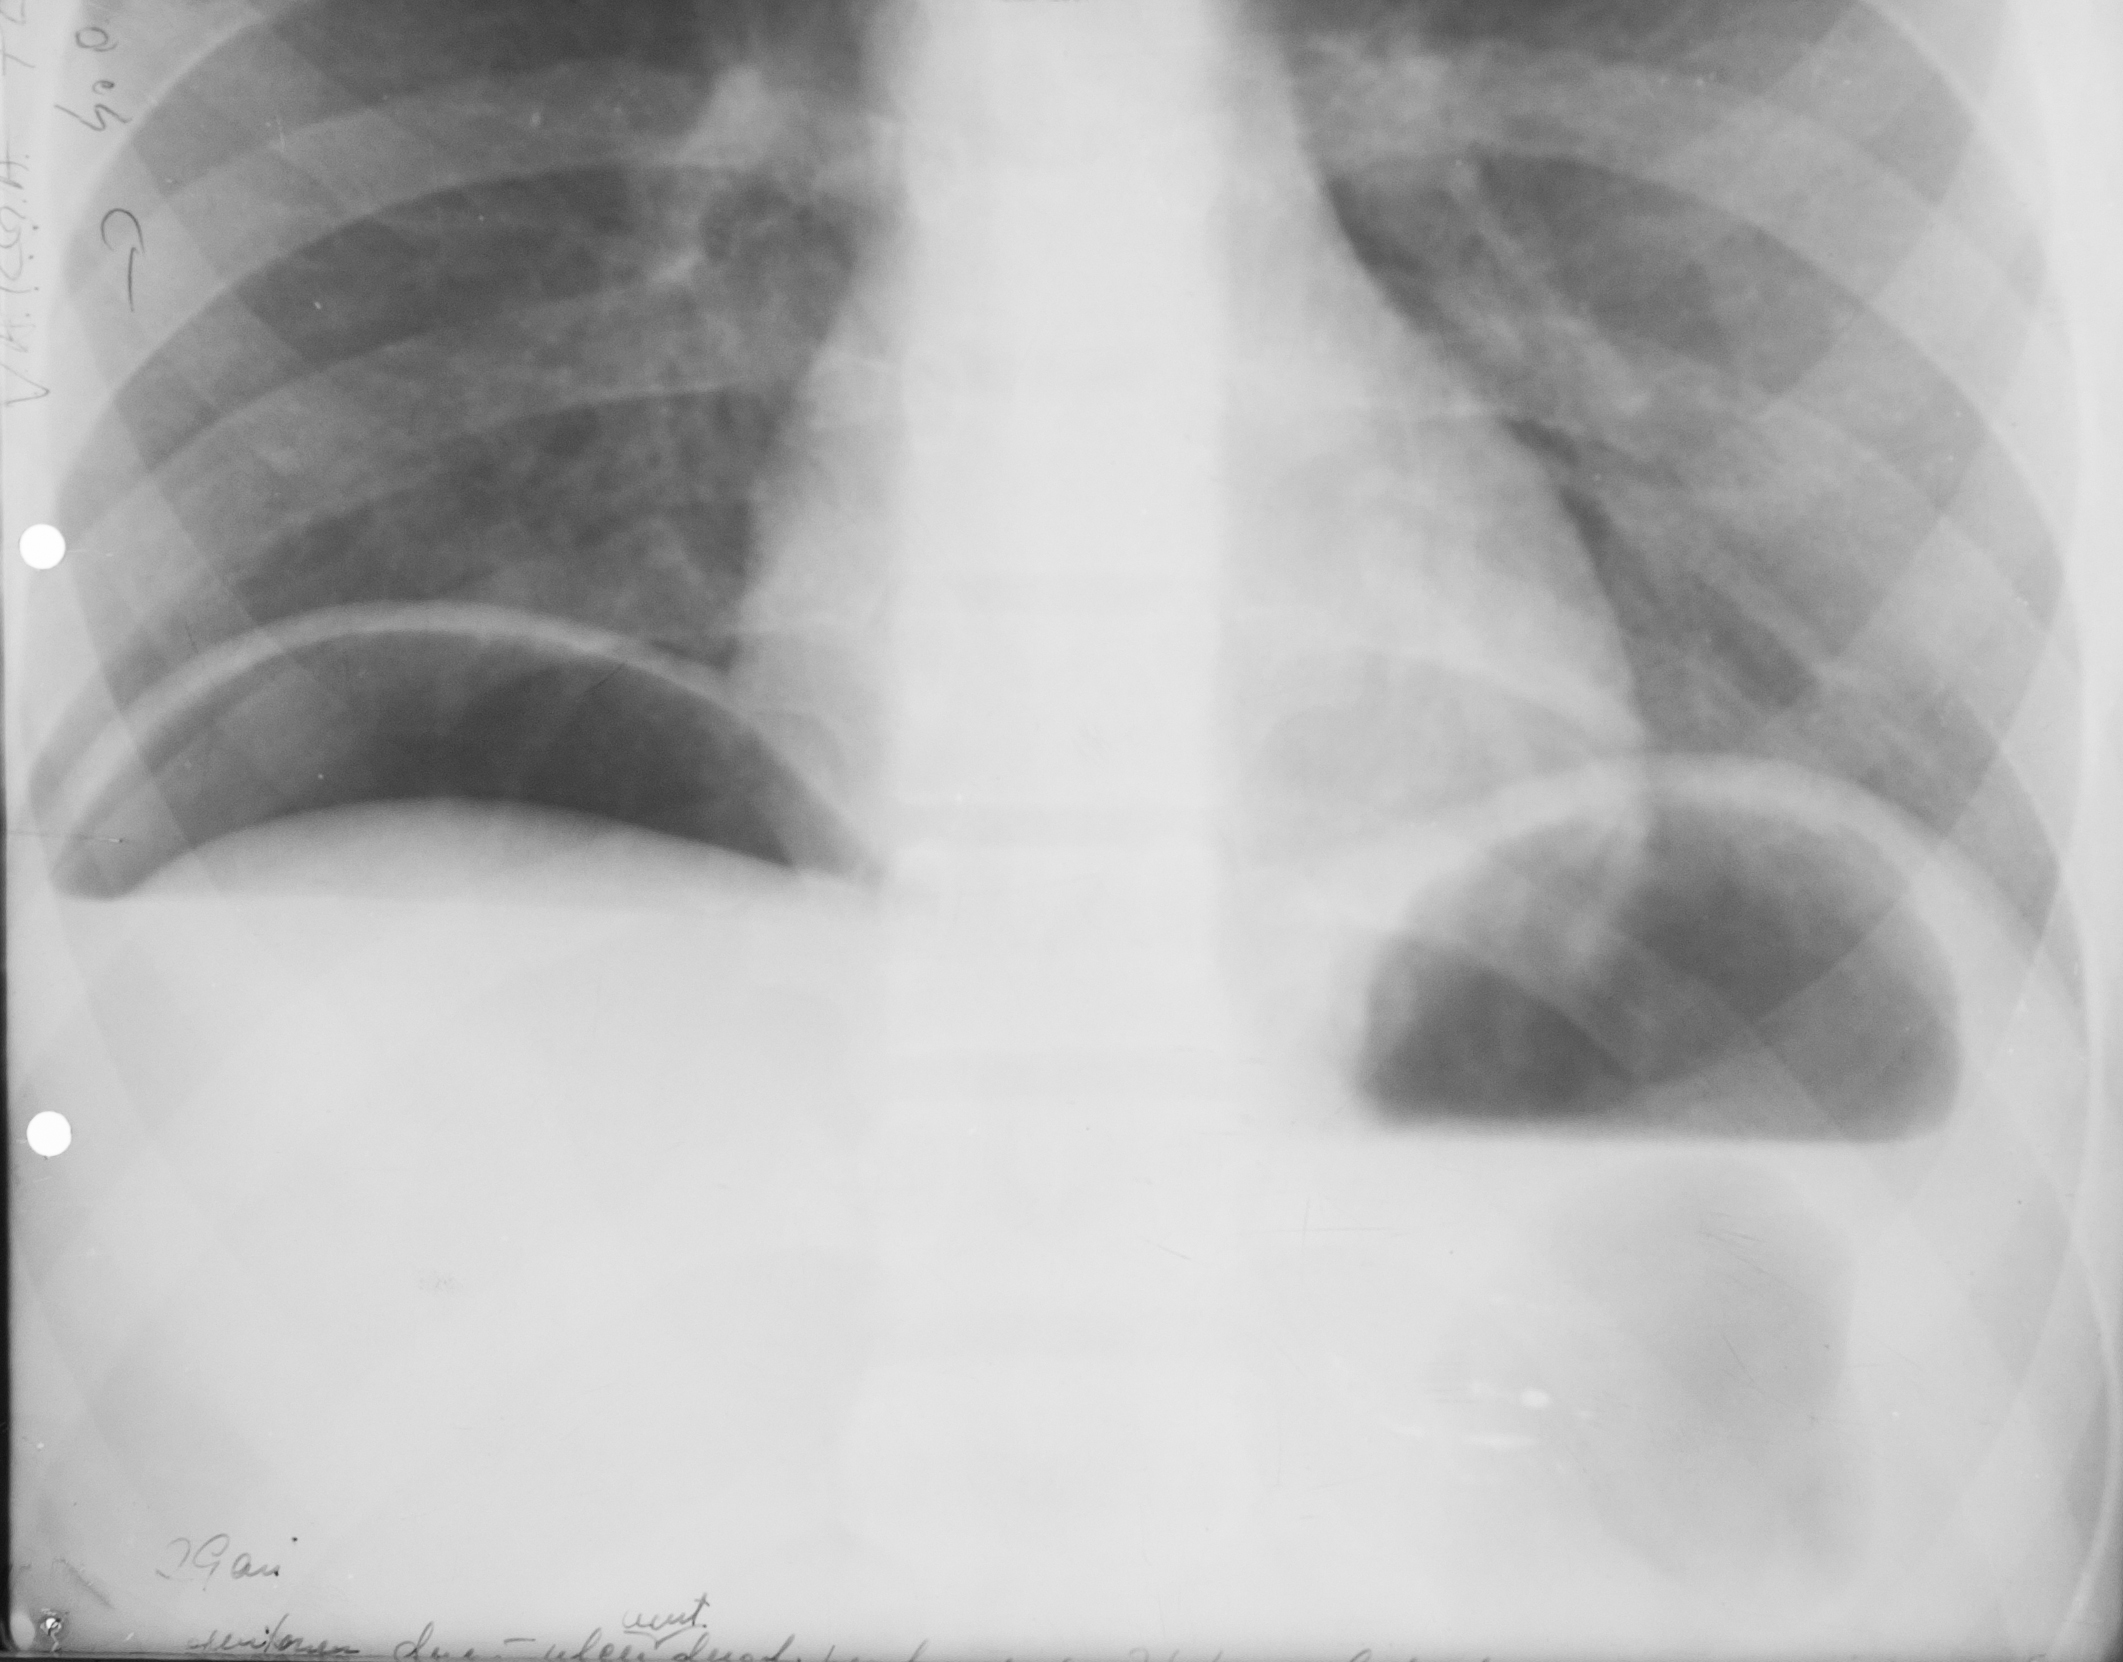

Rx toraco-mediastino-pleuro-pulmonară,incidența de față – vedem o imagine toracică normală (ITN) cu desen pulmonar,cu hil,fara nicio modificare patologică

Rx toraco-mediastino-pleuro-pulmonară – leziunea elementara : opacitate in dreapta,aprox dimensiuni,intensitate similara cu a mediastinului si o alta opacitate paracardiac de dimensiuni mai mari si intensitate mai slaba,nu știm ce sunt,presupunem noduli (sunt 41 de diagnostice diferentiale pt opacitate pulmonară

Rx toraco-mediastino-pleuro-pulmonară – opacitate la bazele plămânilor,de intensitate medie,situată la nivelul sinusurilor costo-diafragmatice,care nu mai sunt ascuțite,ci sunt închise/întinse ?,colecție pleurală

Rx toraco-mediastino-pleuro-pulmonară – opacitate pulmonară în treimea mijlocie a câmpului pulmonar drept,net liniar delimitată inferior, ........... delimitată superior,cu bronho-gramă aerică,cel mai probabil pneumonie

Rx toraco-mediastino-pleuro-pulmonar,de profil – opacitate

Rx toraco-mediastino-pleuro-pulmonară – macroopacitate,problema se pune la localizare : in campul pulmonar apartinand plamanului sau apartinand peretelui toracic – celebrul semn al lui Bernu – opacitate care este tangenta la mediastin,daca face un unghi obtuz cu peretele (unghi de racordaj obtuz),apartine peretelui toracic,iar daca unghiul este ascutit apartine parenchimului pulmonar

Rx toraco-mediastino-pleuro-pulmonar - aici vedem o opacitate tot similară cu aceea,tot net liniar delimitata,dar de data aceasta unghi de racordaj ascutit,inseamna ca apartine campului pulmonar

Rx toraco-mediastino-pleuro-pulmonar – opacități multiple de dimensiuni variabile situate mai degraba la bazele pulmonare,de intensitate medie-slaba,unele mai intense,altele mai putin intense,contururile plu ? – sunt procese de condensare avand in vedere aspectul acesta plu si undeva situat bazal – probabil bronho-pneumonie

METASTAZE PULMONARE

Opacități bine,net liniar delimitate,având aproximativ aceeași intensitate,prezente în ambele câmpuri pulmonare(opacități=procese de condensare).

PNEUMOPERITONEU

Imagine hipertransparenta, semilunara situate sub cupola diafragmatica dreapta